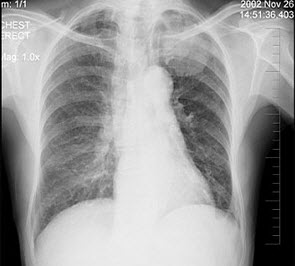

12、单项选择题

女性,51岁,胸痛数月,痰血2天,X线检查见图,最可能的诊断是()

A.左肺癌

B.左侧炎性假瘤

C.左侧纵隔肿瘤

D.左肺转移瘤

E.支气管扩张